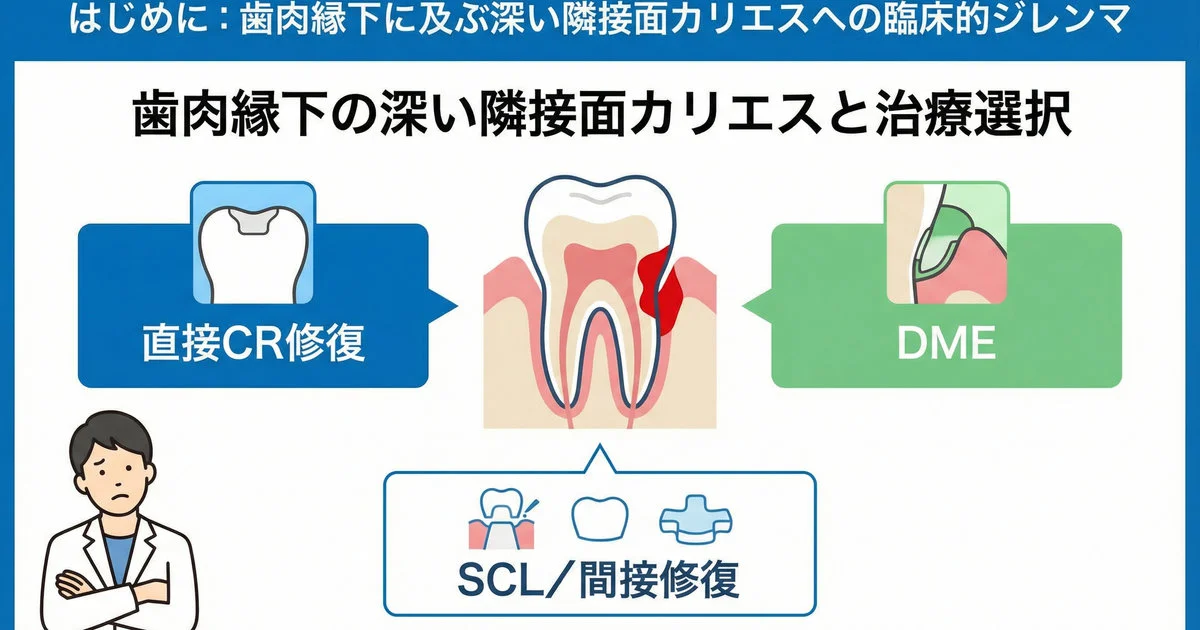

【歯科医師向け】歯肉縁下マージンでも歯を残せるか?|直接CR修復の予後とDME・歯冠長延長術の考え方

深い隣接面カリエスで歯肉縁下にマージンが入り込むと、「このまま直接CRで良いのか」「DMEや歯冠長延長術に踏み切るべきか」と悩む場面が増えます。本記事では、歯肉縁下マージンを有する直接CR修復の予後について、ディープマージンエレベーション(…

続きを読む →